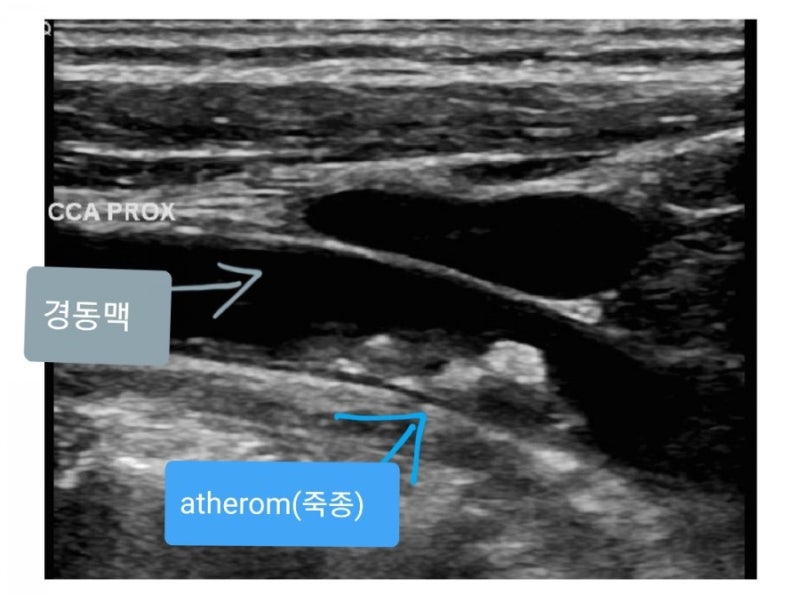

경동맥 초음파 검사는 경동맥 내 혈관의 흐름과 함께 현재 경동맥 상태를 파악하는 데 도움이 되는 검사입니다.

뇌혈관의 약 80%가 통과하는 경동맥을 초음파로 검사하면

뇌에 흐르는 혈액이 감소하는 원인, 혹은 부분적인 동맥 폐색은 없는지, 동맥 협착 등을 가지고 있는지 여부를 조기에 진단할 수 있습니다.

이것은 화면을 통해서 경동맥의 상태를 파악할 수 있기 때문에 만약 진행 중에 문제가 발생했다고 생각되는 부분이 있다면

좀 더 자세히 관찰하는 시간이 필요하기 때문에 길게는 40분 정도의 시간이 걸릴 수도 있습니다.

만약 경동맥 내막 두께가 1.0mm 이상이라면 서둘러 치료를 시작하는 것이 돌연사 예방은 물론 치료 예후가 좋습니다.